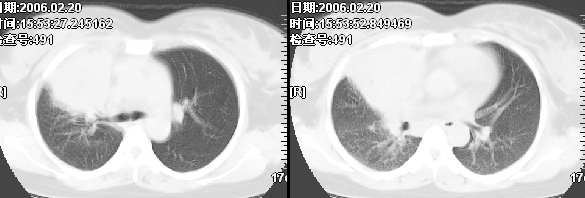

女,28岁咳嗽无痰偶有低烧,化验:白细胞1万零7,血沉正常

图象不错,无肺窗。右肺上叶前段支气管呈鼠尾样,边缘尚光滑,气管前淋巴结肿大,未见空气支气管征考虑占位性病变可能。与大叶性肺炎和早期肺脓肿鉴别,建议抗炎后复查。

右肺上叶前段与中叶见较大团块影。边界较清晰,纵隔隆突前淋巴结增大。考虑1肺部间叶组织肿瘤可能。2感染性病变

我觉得不要把患者年龄作为轻易排除肺癌的依据,病变呈大块状软组织密度,右肺中叶支气管可见中断,右侧肺门增大,要高度警惕肺癌,支气管镜应该能够给出正确的诊断。间质来源的恶性肿瘤尽管可以考虑到,但是从发病率上来说不首先考虑。

补充病例结果是:肺间变大t细胞淋巴瘤. 非霍奇金淋巴瘤(间变大t细胞性)iv期bipi 2分

右肺中下叶切除